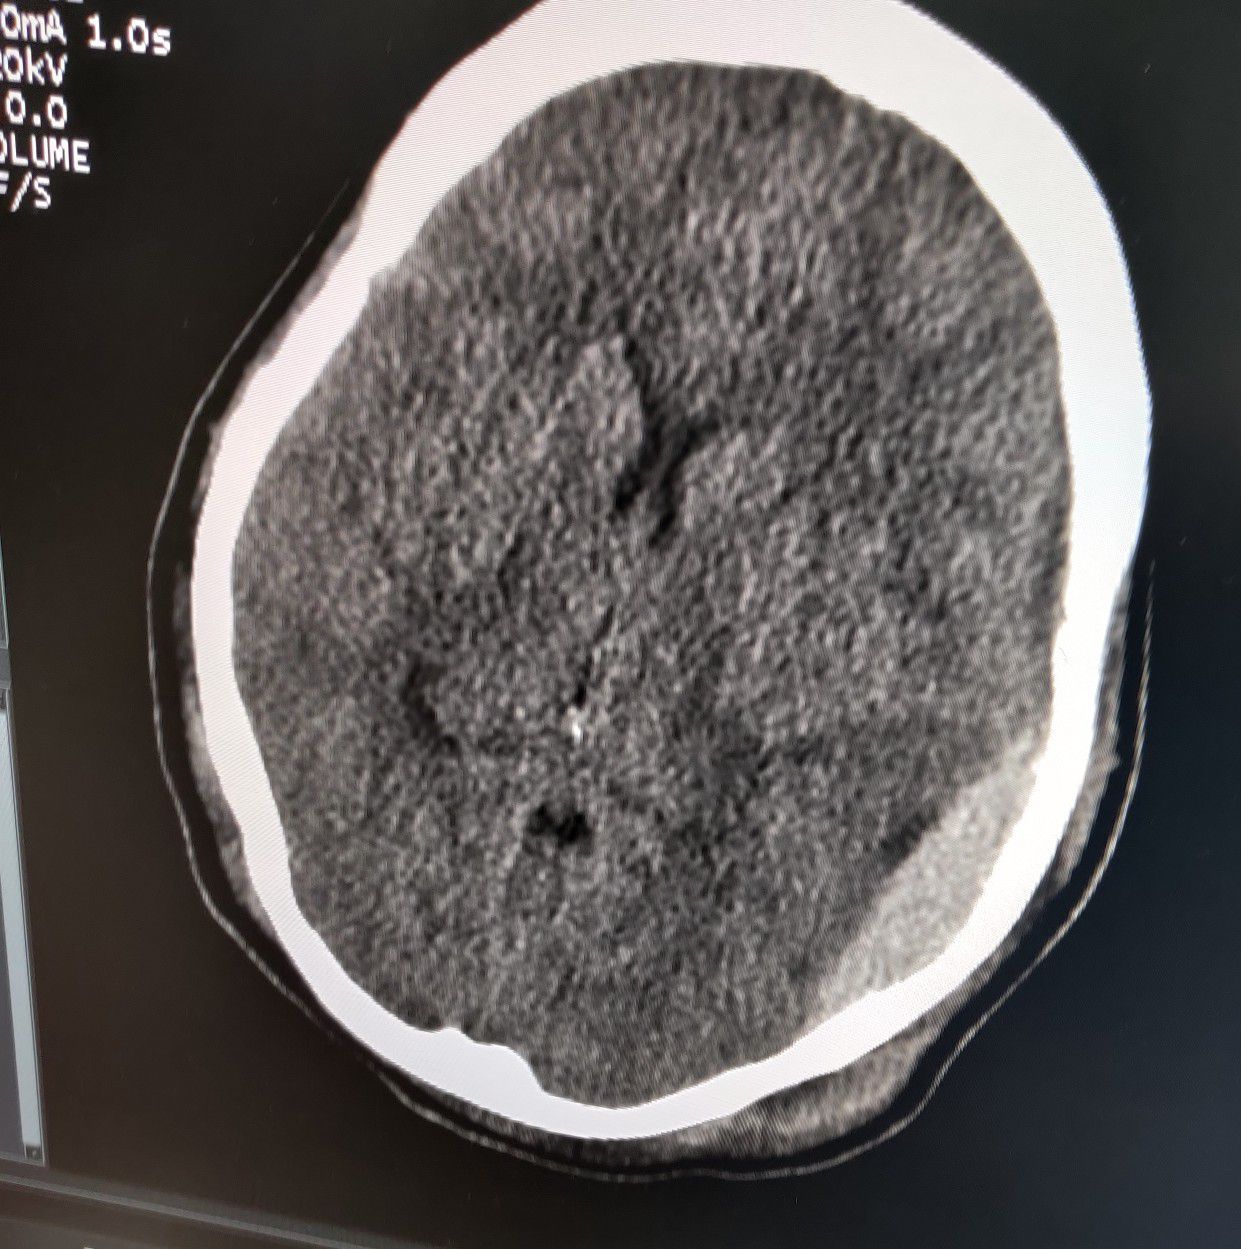

Epidural Hematoma

Rta

Headinjury

Ctbrain